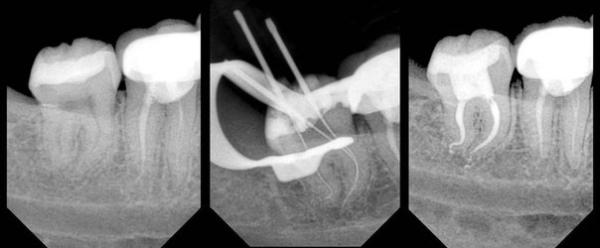

Разветвление каналов при нестандартном строении корневой системы

Встречаются случаи, когда каналов в зубе больше, чем корней. Задача стоматолога — провести полную диагностику, выявить и заполнить все существующие каналы. При упущении даже одного, возникает воспаление. Такие ситуации встречаются нечасто и зависят от квалификации специалиста.

Фото 1. Рентгеновский снимок зуба с сильно искривлёнными каналами во время и после лечения.